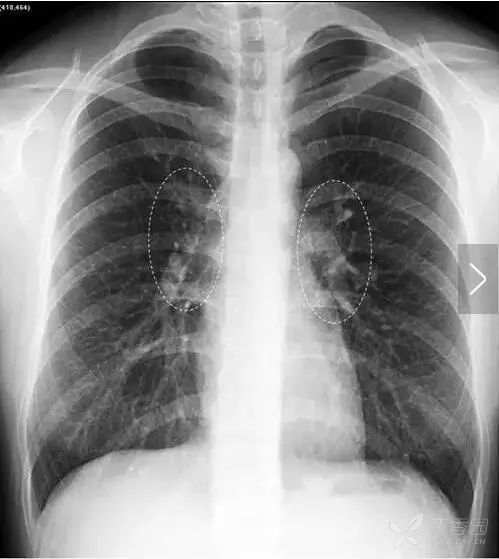

肺门

胸部X线平片所指的肺门即肺动静脉及气管等进出肺的部位的诸结构的投影,当然,左、右肺分别有各自的肺门(图8)。

图8 左、右肺门(虚线椭圆范围内)为肺动静脉及气管等进出肺的部位诸结构的投影 。